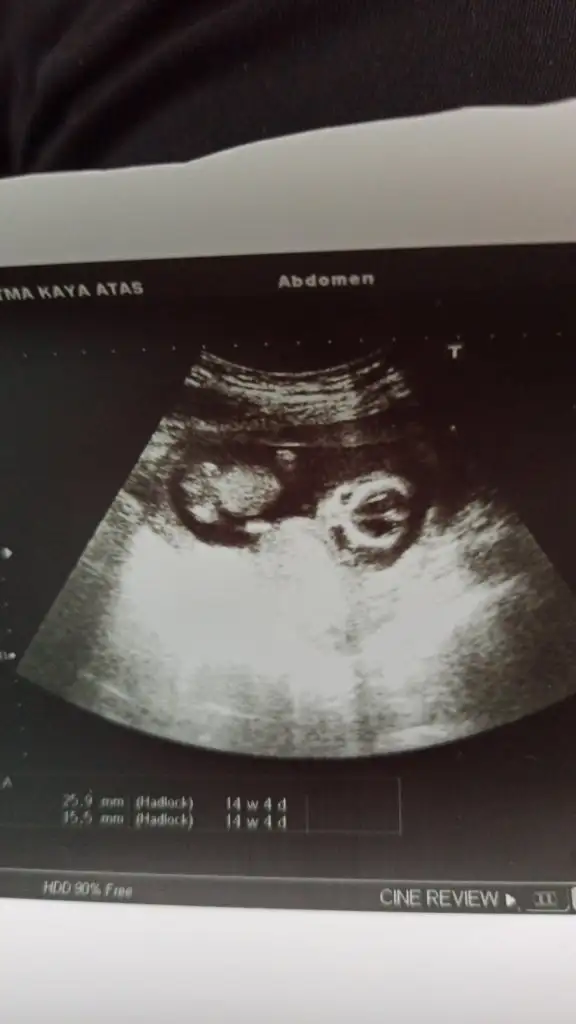

Ayyyyy büyümüş ya bu... Yesin teyzesi onunyaaa MashaAllah kuzuma..11+2 de olan görüntümüz karından bakıldı bana da bi tahminde bulunur musunuz![]()

kız gibi duruyor canımHayırlı geceler kızlar14+1 ken doktorum%80 kız demişti sizde bakar mısınız sonuç degismz demi kızım olsun istiyorum

![]()